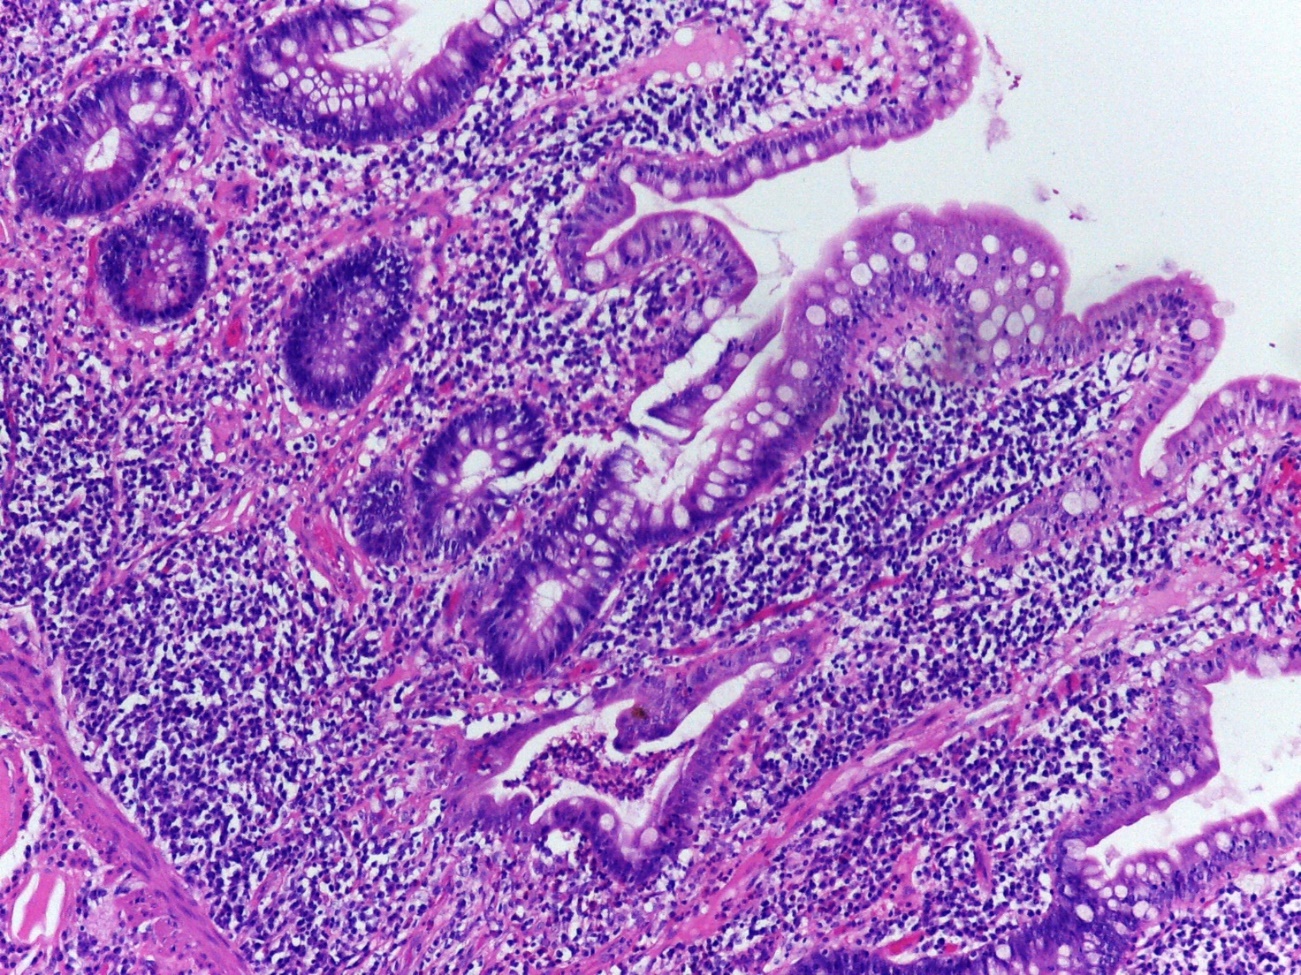

Pouchitis refers to an inflammatory condition affecting the ileal pouch, commonly observed in individuals who have undergone proctocolectomy. The pouchitis market has experienced remarkable growth recently. The increasing prevalence of inflammatory bowel diseases (IBD), including ulcerative colitis and Crohn's disease, serves as a primary driver for the pouchitis market. This rise necessitates the development of effective therapeutic solutions, leading to the creation and availability of new medications. Advanced research and technological progress in the medical field have resulted in the introduction of innovative diagnostic tools and treatments. These advancements improve the accuracy and efficiency of pouchitis diagnosis and management, ultimately enhancing patient outcomes and contributing to market expansion. Growing healthcare expenditures in various countries are enabling increased investments in R&D activities. This boost in funding plays a crucial role in discovering novel therapeutic approaches and medications, further strengthening the pouchitis market.